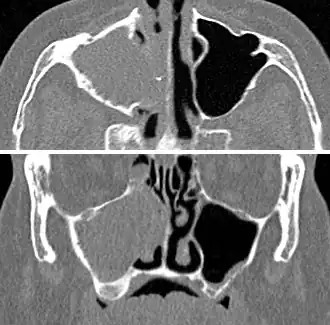

Imaging by either X-ray, CT, or MRI is generally not recommended unless complications develop.[66] Pain caused by sinusitis is sometimes confused for pain caused by pulpitis (toothache) of the maxillary teeth, and vice versa. Classically, the increased pain when tilting the head forwards separates sinusitis from pulpitis.[68]

For cases of maxillary sinusitis, limited field CBCT imaging, as compared to periapical radiographs, improves the ability to detect the teeth as the sources for sinusitis. A coronal CT picture may also be useful.[60]

For sinusitis lasting more than 12 weeks, a CT scan is recommended.[66] On a CT scan, acute sinus secretions have a radiodensity of 10 to 25 Hounsfield units (HU). In a more chronic state, they become more viscous, with a radiodensity of 30 to 60 HU.[69]